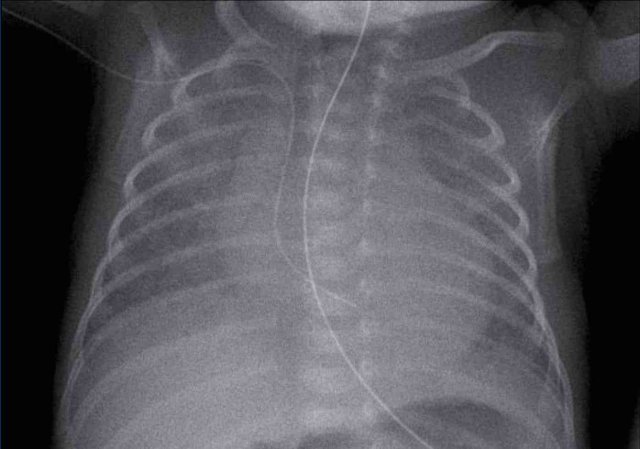

Neonate 32 weeks gestational age. Treated for RDS via CPAP, with sudden respiratory distress.

First study the image.

What are the findings?

Image

There is a  a pneumothorax on the right side.

Midline structures are displaced to the left.

The left lungs shows reticulonodular markings in keeping with RDS.

The right lung is not completely collapsed due to stiffness of the parenchyma in RDS and fluid.